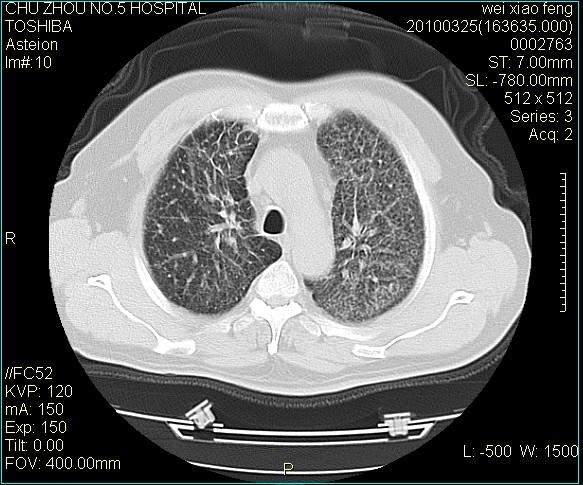

男,60岁,反复咳、痰、喘3月,加重3天。

双肺间质性改变。

考虑双肺血型潘散肺结核/

间质性肺炎伴间质纤维化!不排除伴有职业病!

双肺间质纤维化,双肺血型潘散肺结核。

考虑间质性肺炎伴间质纤维化。

间质病变,间质炎症,间质纤维化趋势

右肺中叶结节影为原发灶,考虑右肺中叶周围型肺癌并淋巴道转移

间质性肺炎